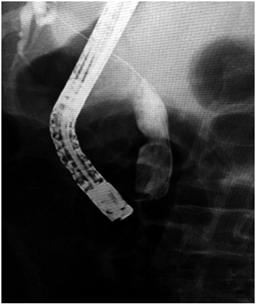

Los factores de riesgo asociados con el procedimiento que pueden estar relacionados con la presencia de eventos adversos incluyen el tamaño de la EFT, el diámetro del balón utilizado y la forma de inflar el balón 8,9,14. El diámetro del conducto biliar distal es el factor más importante al seleccionar el diámetro del balón que se va a utilizar, ya que la dilatación más allá del diámetro del colédoco aumenta el riesgo de perforación y, por ende, el diámetro máximo de inflado del balón no debe exceder el diámetro mayor del colédoco distal. Aunque el diámetro de los balones para DPBG oscila de 12 mm a 20 mm, en la mayoría de los casos se utilizan balones de 12 mm a 15 mm para prevenir eventos adversos (Figura 3). El inflado rápido y forzado del balón a través de un conducto biliar distal estrecho puede llevar a perforación y sangrado. Por esto, el balón siempre debe inflarse lenta y gradualmente hasta que desaparezca su cintura (Figura 4). Si la cintura del balón no desaparece, puede sugerir la presencia de una estenosis biliar oscura (oculta), y no se debe dilatar por encima de este nivel. En ese caso, se debe desinflar el balón para evitar el riesgo de complicaciones. En los pacientes con estenosis biliares evidentes, o en conductos no dilatados, la DPBG no se recomienda debido al riesgo de perforación 17,18. La duración usual de la DPBG es de 30 a 60 segundos después de desaparecer la cintura, aunque en diferentes estudios respecto del tiempo de dilatación oscilan entre los 10 segundos y los 180 segundos 14,18; se requieren estudios adicionales para establecer la duración óptima de la dilatación. En nuestra serie, el tiempo de dilatación fue de 60 segundos.